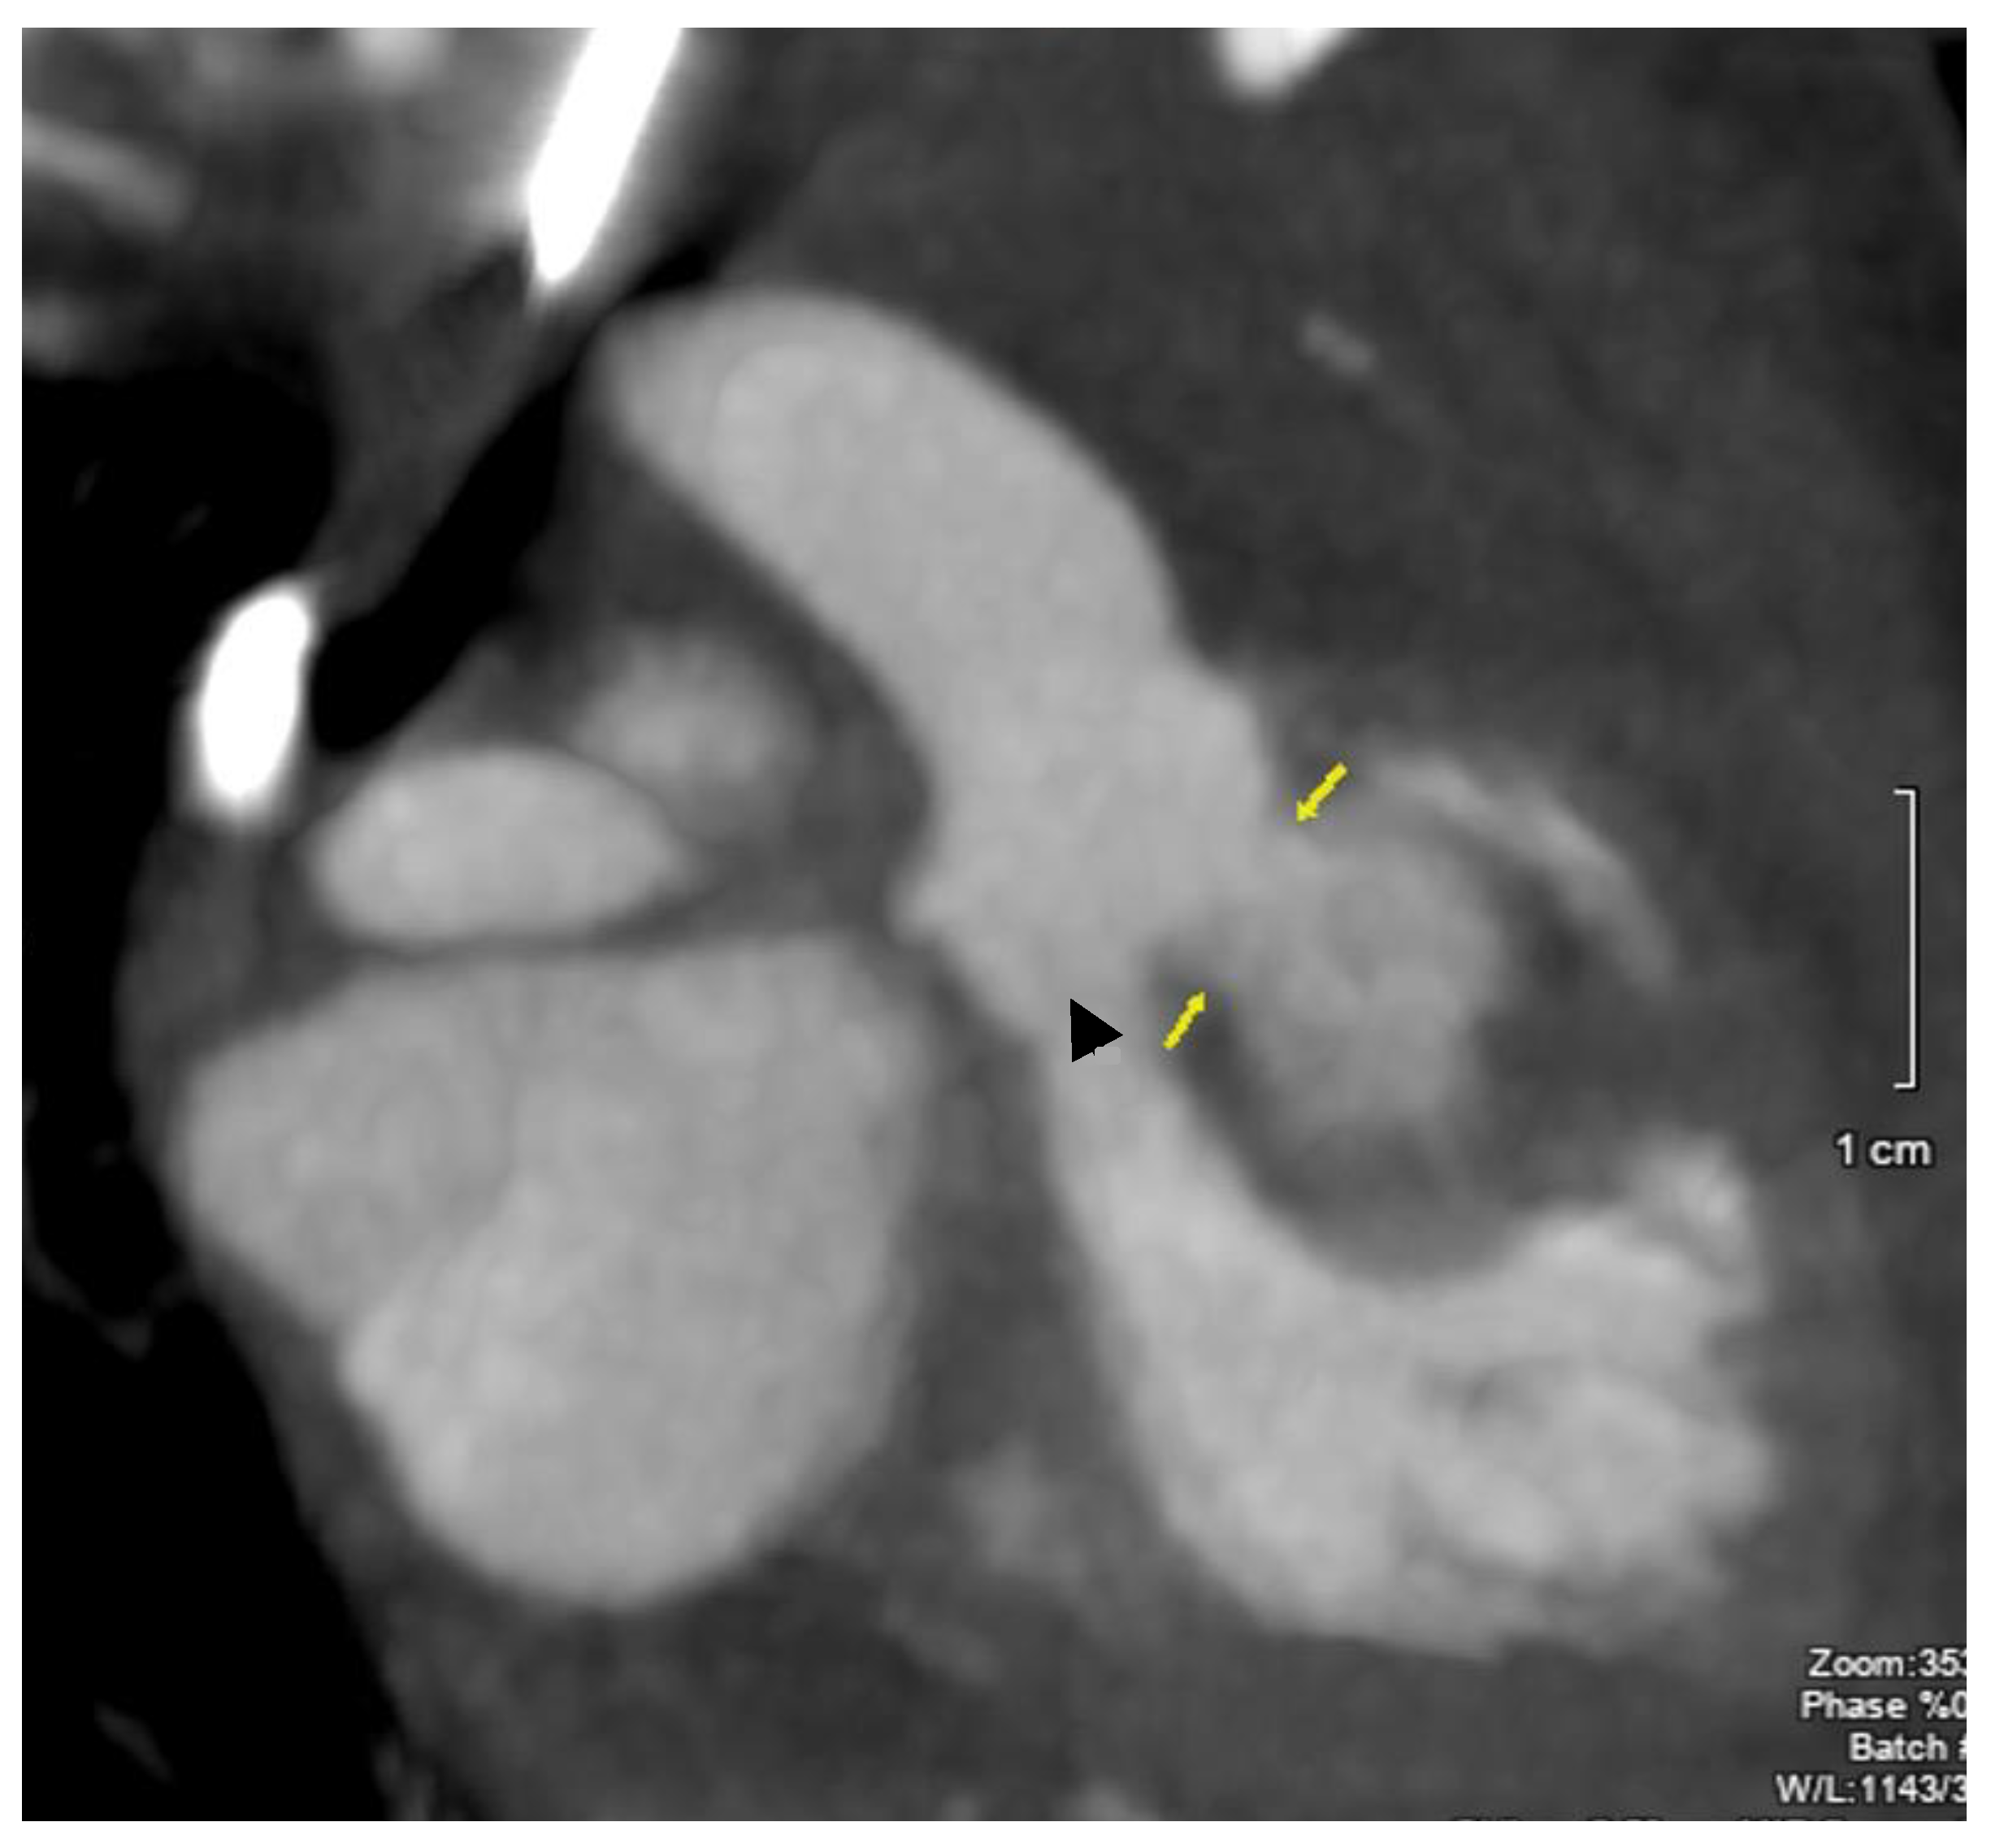

2. Case Description